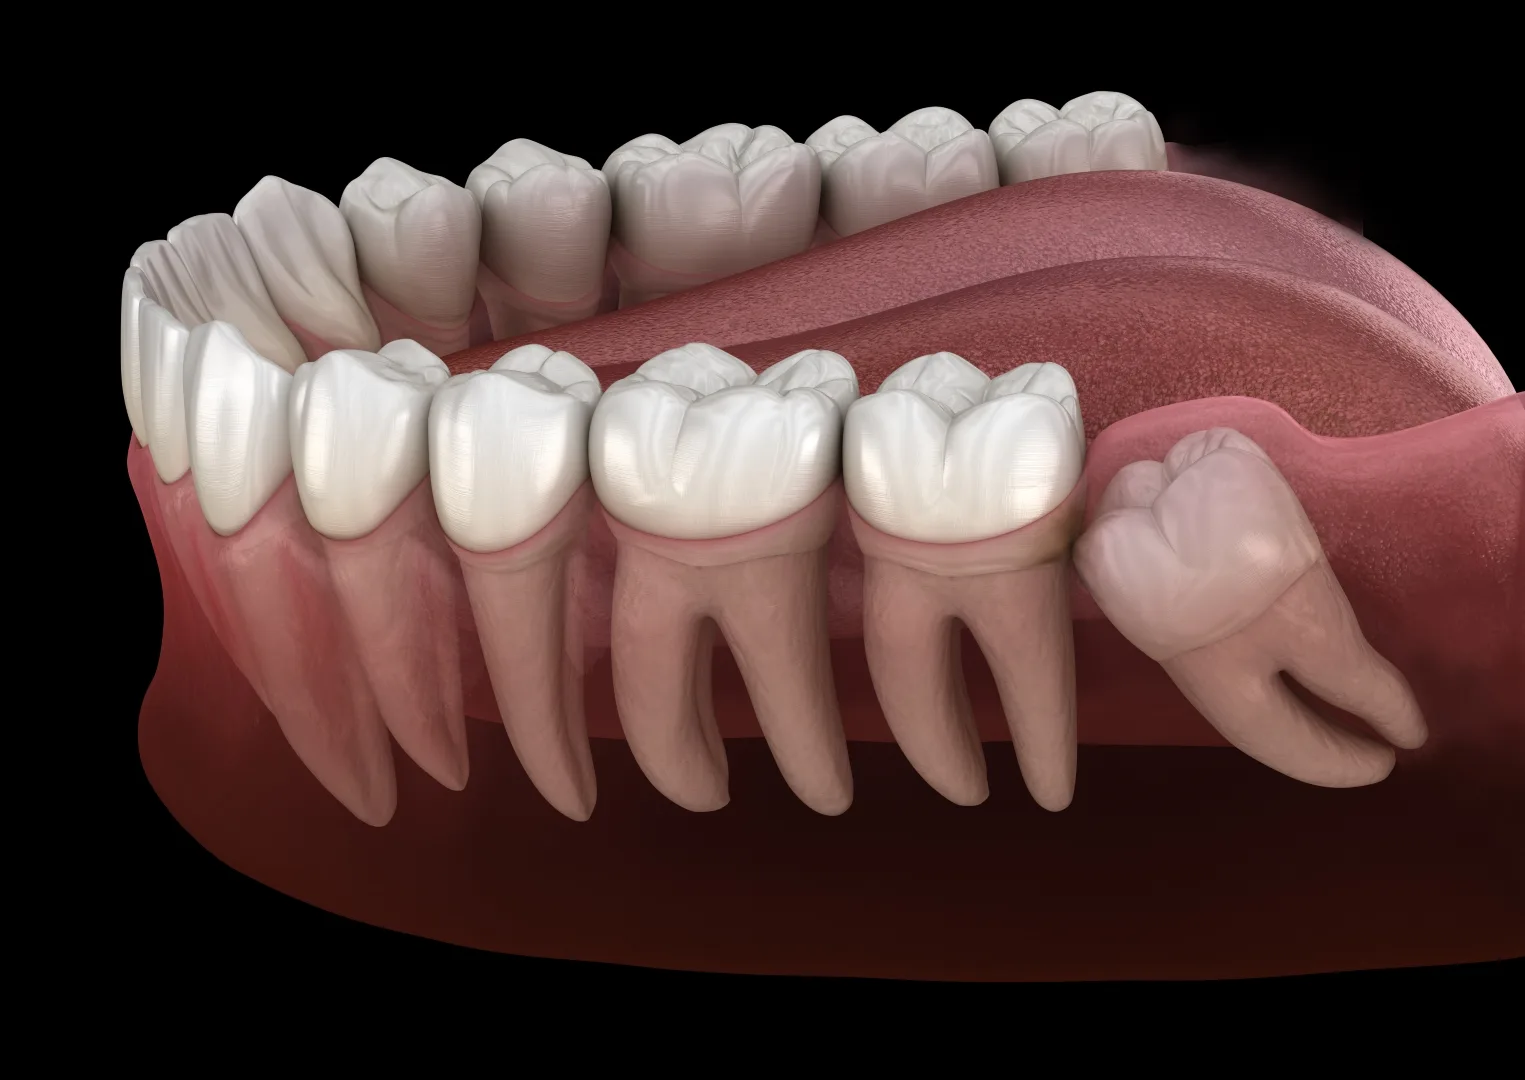

Wisdom teeth are the last adult teeth to come in, usually erupting between the ages of 15 and 25. While a lucky few have enough room in their mouths to accommodate these third molars, the majority of people don’t. This means that the wisdom teeth grow sideways, get stuck in the gums or jawbone, or crowd out the rest of your teeth.

That’s why it’s important to schedule an appointment at our office to evaluate your wisdom teeth at an early age. It’s best to not wait until they are erupting or noticeable in your mouth. At this appointment, Dr. Leavitt’s team will take a 3D X-ray, check your wisdom teeth, and evaluate the benefits of removing them. We will also consider the impact the procedure might have on your long-term oral health to determine whether extraction is necessary.